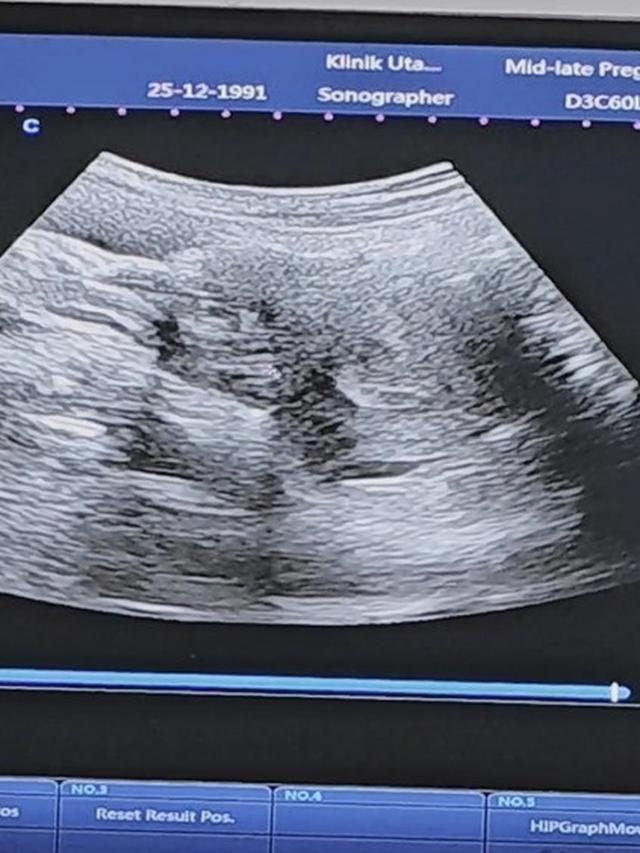

Dude Harlino turut serta mengantar dan menemani Alyssa Soebandono ke dokter kandungan untuk melakukan pemeriksaan terkait kehamilan anak ketiga mereka.

Dengan rutin, mereka bersama-sama mengunjungi dokter kandungan untuk memastikan kesehatan Alyssa Soebandono dan calon anak ketiga mereka. Keberlanjutan pemeriksaan ini menjadi langkah penting dalam memastikan kesejahteraan kesehatan ibu hamil dan perkembangan yang baik bagi calon anggota keluarga.